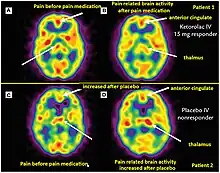

Positron emission tomography (PET) imaging in theranostics provides insight into metabolic and molecular processes within the body. The PET scanner detects photons and creates three-dimensional images that enable visualization and quantification of physiological and biochemical processes.[11] PET imaging uses radiotracers that target specific molecules or processes. For example, [18F] fluorodeoxyglucose (FDG) is commonly used to assess glucose metabolism, as cancer cells exhibit increased glucose uptake. Other radiotracers target specific receptors, enzymes, or transporters, allowing the evaluation of various physiological and pathological processes.[11]

PET imaging plays a role in both diagnosis and treatment planning. It aids in the identification and staging of diseases, such as cancer, by visualizing the extent and metabolic activity of tumors. PET scans can also guide treatment decisions by assessing treatment response and monitoring disease progression. Additionally, PET imaging is used to determine the suitability of patients for targeted therapies based on specific molecular characteristics, enabling personalized treatment approaches. [12]